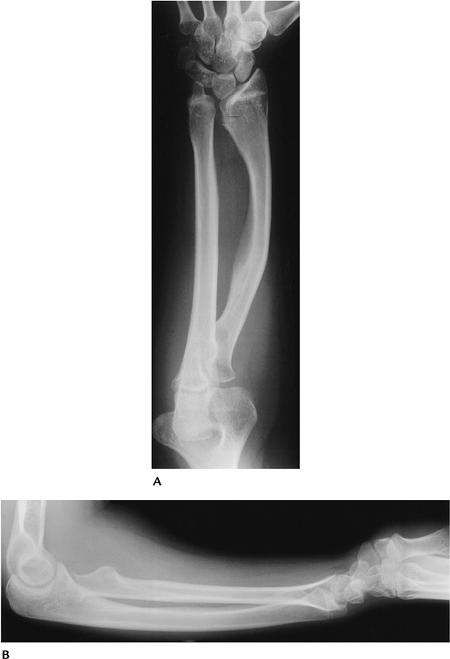

FIGURE 15-30 Dyschondrosteosis (Leri-Weill syndrome). AP (A) and lateral (B)

radiographs of the forearm showing Madelung deformity with bowing of the radius and a V-shaped radioulnar articular surface with carpal bones collapsed centrally. |